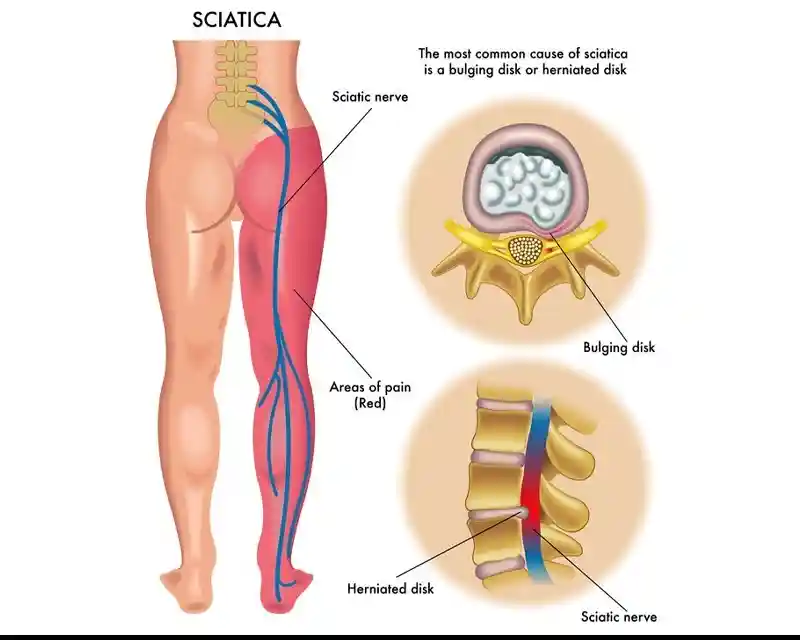

Sciatica is a painful condition caused by compression or irritation of the sciatic nerve, which runs from the lower back through the hips and down each leg. It often results in pain, numbness, or a burning sensation in the lower back, buttocks, and legs.